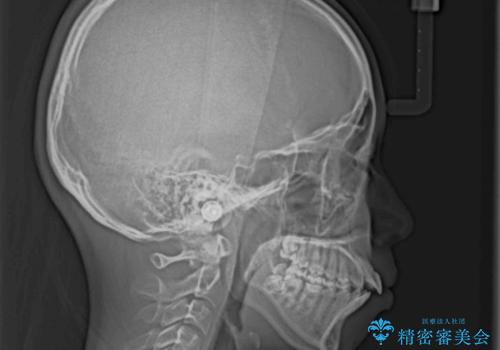

- 上下の出っ歯を気にして来院された患者様です。

口元を積極的に引っ込めるために、上下左右の第一小臼歯を4本抜歯することとしました。

前歯部の突出と開咬は、舌突出癖によるものでしたので、舌のトレーニングをしっかりと行っていただき、1年半程度と短期間で治療を終えることができました。